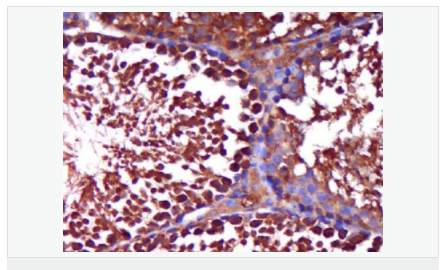

| 产品应用 | WB=1:500-2000 ELISA=1:5000-10000 IHC-P=1:100-500 IHC-F=1:100-500 Flow-Cyt=1ug/Test IF=1:100-500 (石蜡切片需做抗原修复) not yet tested in other applications. optimal dilutions/concentrations should be determined by the end user. |

| 细胞定位 | 细胞核 细胞浆 |